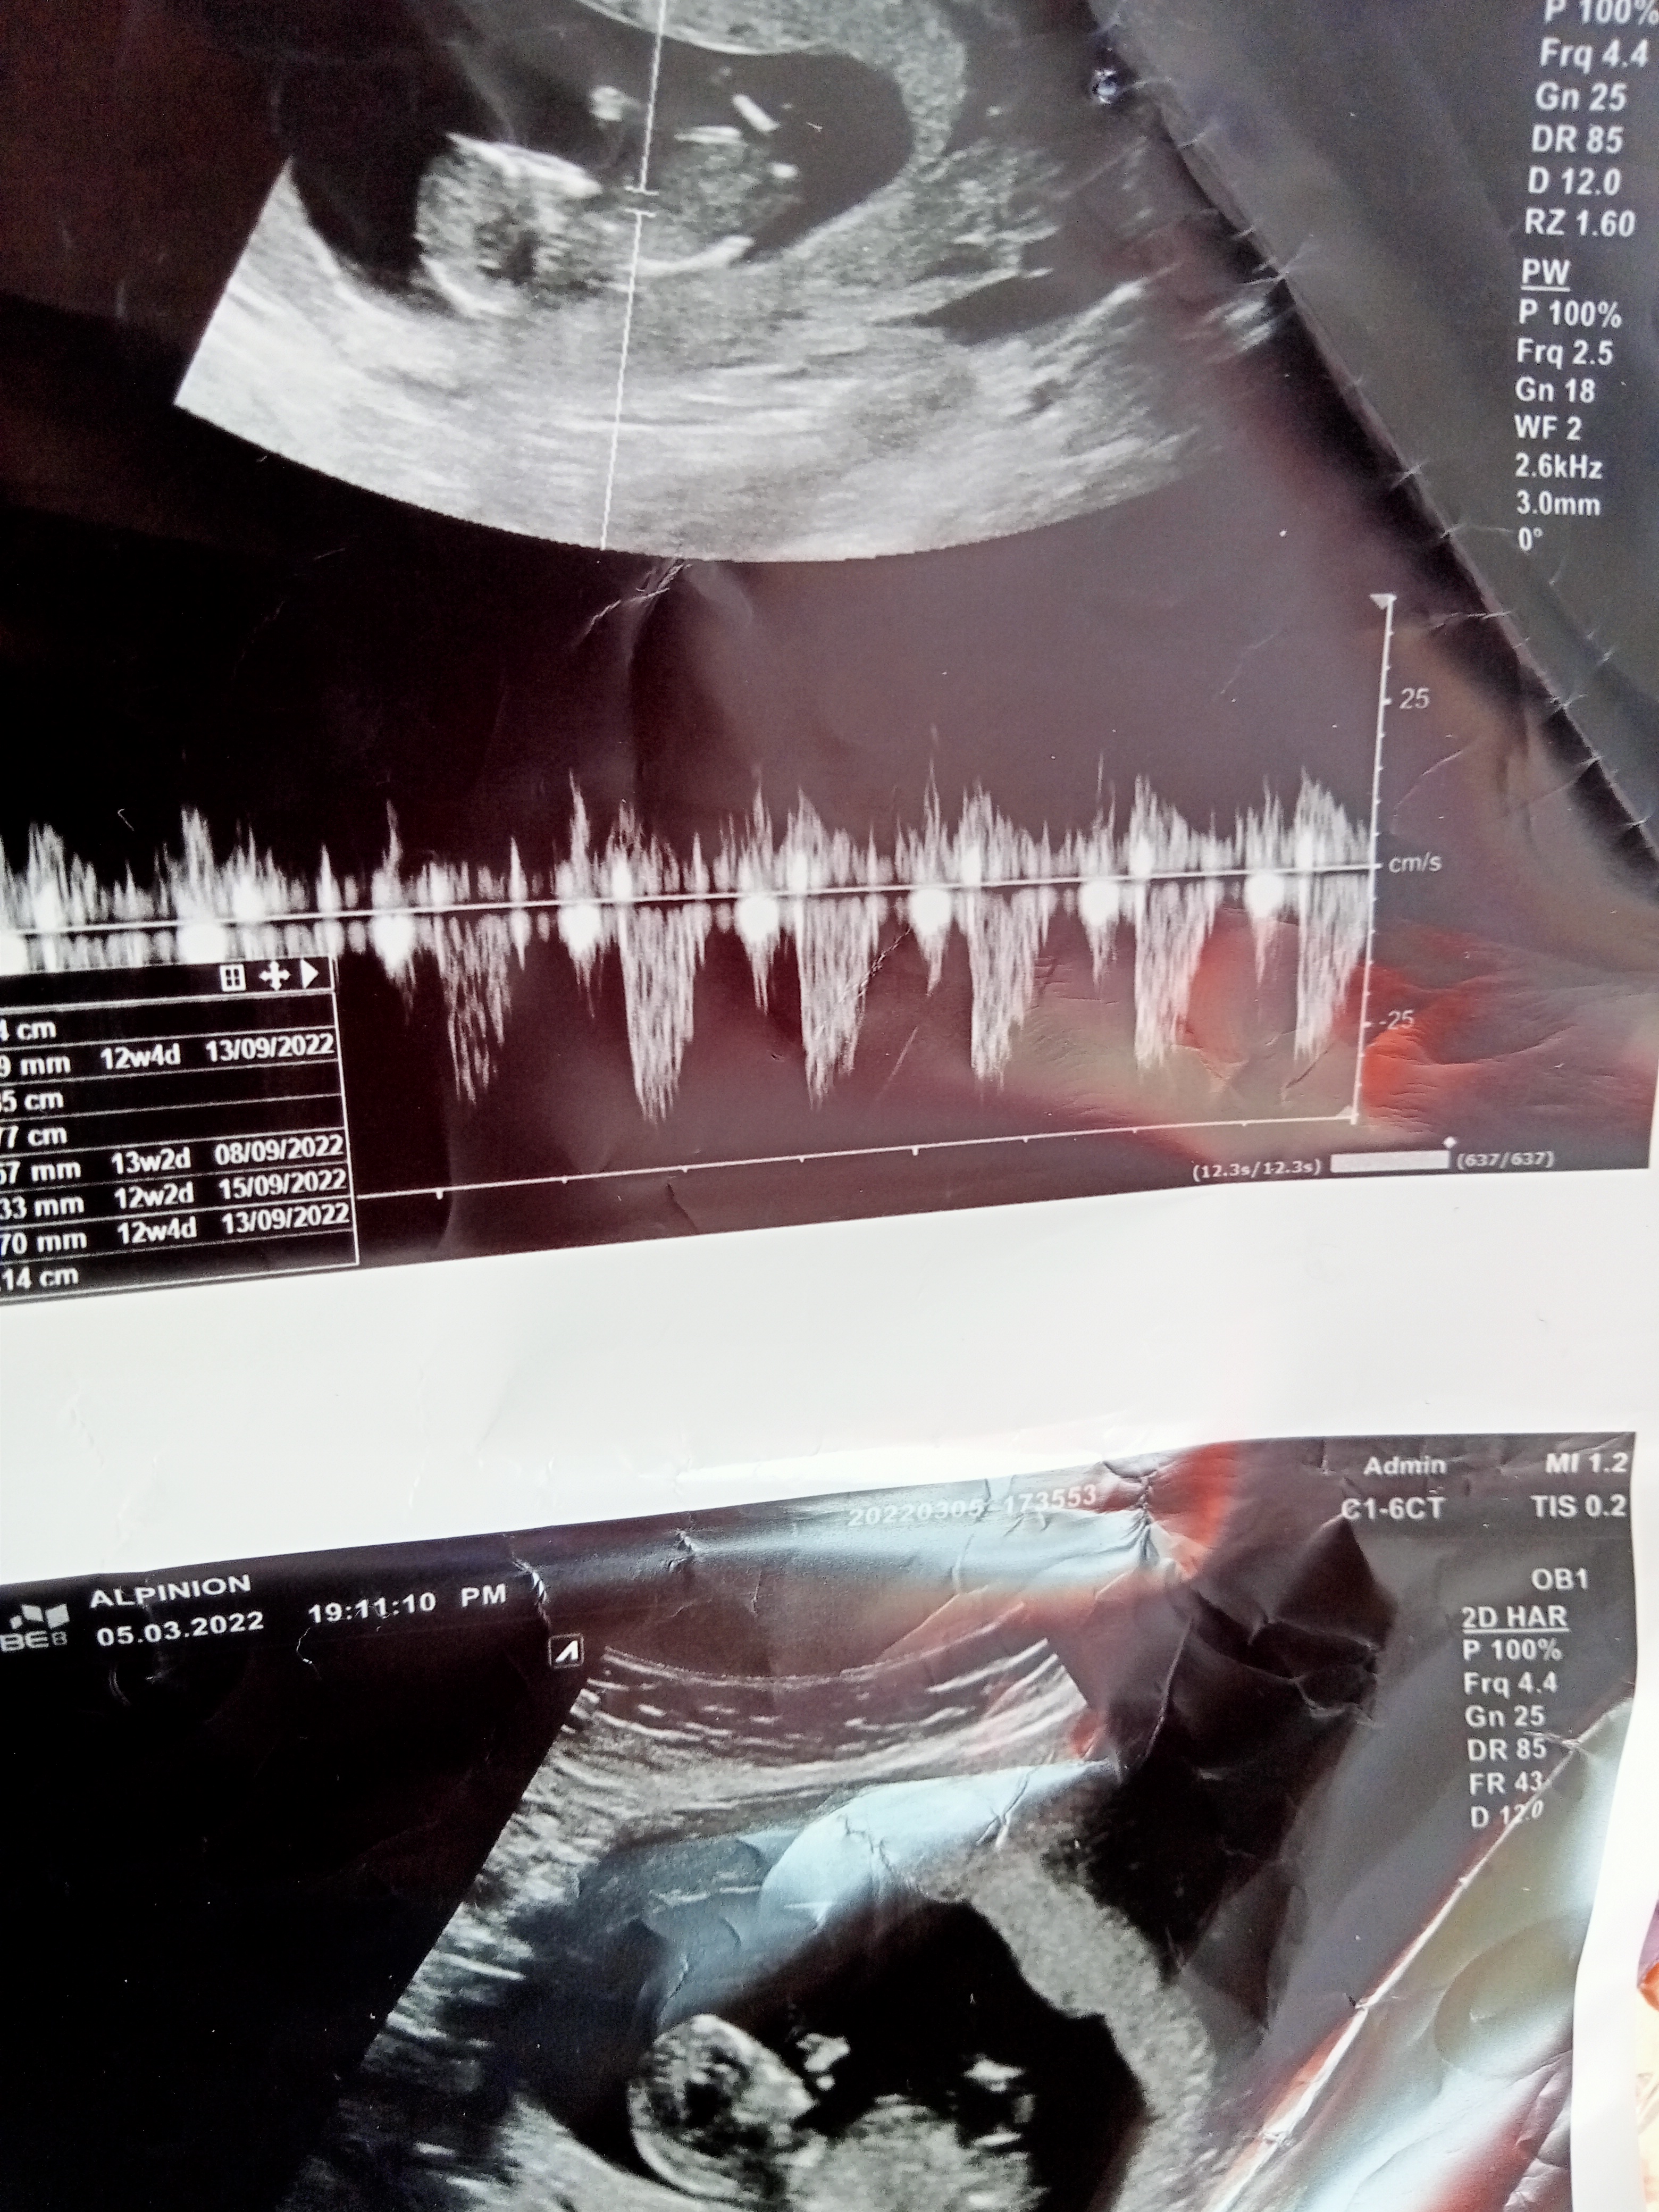

Baş şekli vücud şeklinden tahmininiz olurmu acaba teşekkürlerSelamlar Sevgili Nermin, Resmi baya inceledim ama görmemiz gereken genital tüberkülül görünmüyor dolayısı ile bir cinsiyet tahmini malesef yapamıyorum. Başka resim var ise yükleyin onlara da bakalım olur mu ?